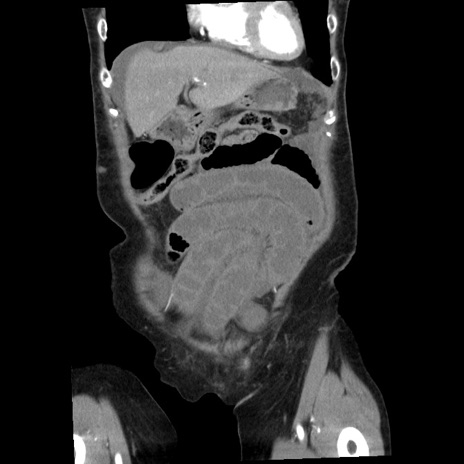

矢状断像

【症例】80歳代女性

【主訴】腹痛

【現病歴】8時間前から腹痛あり来院。

【既往歴】糖尿病、脂質異常症、子宮体癌にて子宮全摘術

【身体所見】意識清明・会話良好だが腹痛で苦悶様、全腹部にわたって反跳痛と圧痛あり

【データ】WBC 13600、CRP 0.14、LDH 224、CK 90